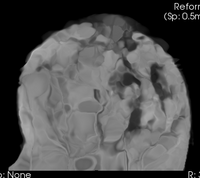

this is the fixed reference image: PreRx Breast MRI with large tumor mass lleft this is the moving image, to be registered with the reference above: PostRx Breast MRI with tumor largely absent

fixed image/target

pre Rx MRI